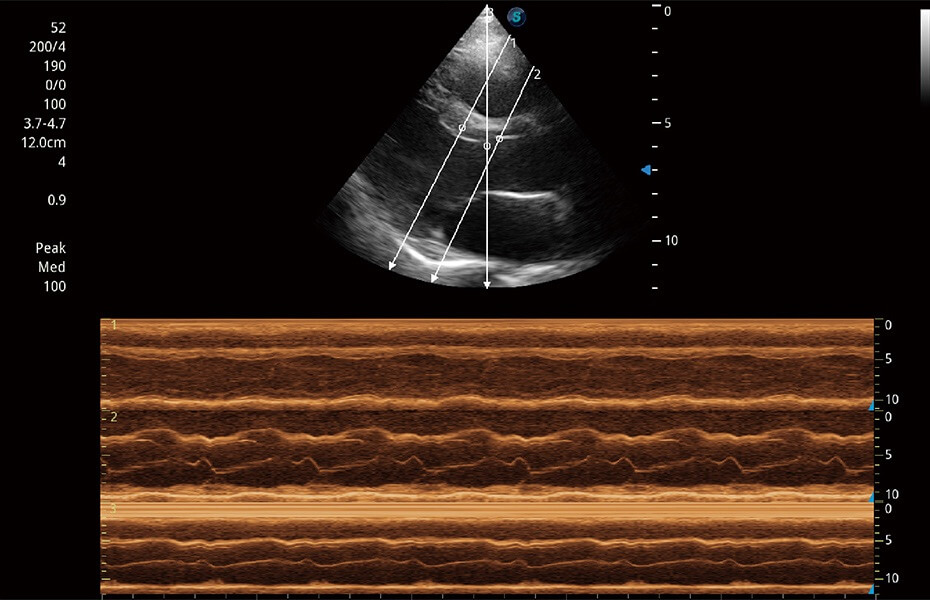

ProPet 60 作為一款高端臺(tái)式動(dòng)物超聲設(shè)備,為動(dòng)物醫(yī)生的日常診斷提供了一系列貼合動(dòng)物臨床需求、解決臨床實(shí)際問(wèn)題的高級(jí)成像功能。憑借全系列高清探頭,滿足醫(yī)生對(duì)腹部、心臟、生殖、淺表、肌骨等成像的所有需求,切實(shí)幫助您提升檢查效率,提高診斷信心。